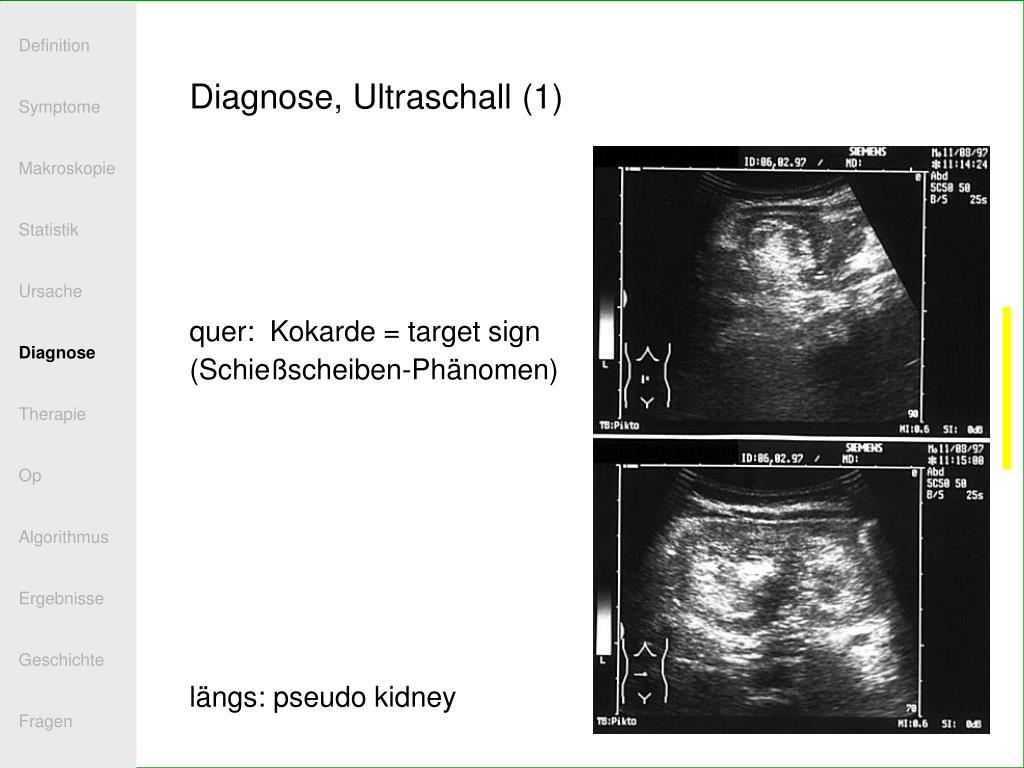

28. Definition Symptome Makroskopie Statistik Ursache Diagnose Therapie Op Algorithmus Ergebnisse Geschichte Fragen Diagnose, Ultraschall (1) quer: Kokarde = target sign (Schießscheiben-Phänomen) längs: pseudo kidney

29. Definition Symptome Makroskopie Statistik Ursache Diagnose Therapie Op Algorithmus Ergebnisse Geschichte Fragen Diagnose, Ultraschall (2) Kokarde = target sign = Schießscheiben- Phänomen